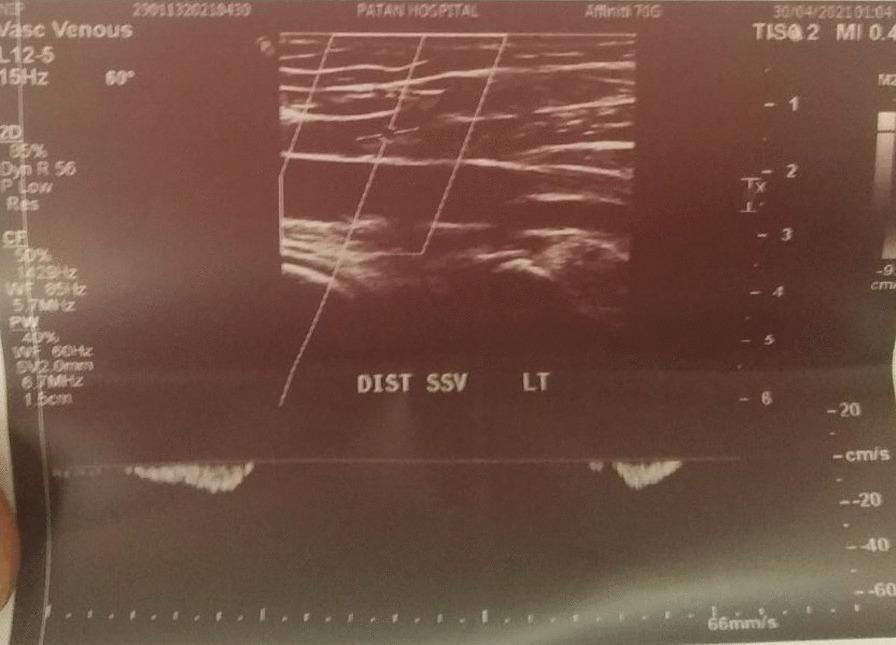

Two cases, a 24-year-old young Chhetri male and a 62-year-old Chhetri female who have received Covishield (ChAdOx1 nCoV-19) vaccine, developed pain in left calf after 2 weeks and 10 weeks of vaccination, respectively. Both the case belongs to the Chhetri ethnic group of Nepal. The pain became severe on the fourth week of immunization in the first case while the pain was acute and severe on the 10 week of vaccination in the second case. The first presented to emergency room and second case was referred to the emergency room from Orthopedic Clinic. On evaluation the first patient had normal vitals with no history of fever and swelling yet displayed non-radiating mild to moderate intensity pain localized to left leg below the knee which became aggravated by movements. In the second case however pain was more intense with other characteristics as first case. Both cases had low wells score (< 4). On local examination tenderness was noted on squeezing but other systemic examination findings of the patient were within normal limits in both cases. Among the numerous vaccines used to fight the battle against COVID-19 disease, the ChAdOx1 nCoV-19 vaccine, Covishield, has been widely used in Nepal and India. Apart from other minor side effects, in few cases thromboses have been reported after vaccination of ChAdOx1 nCoV-19, Covishield, vaccine.

两例患者均为尼泊尔 Chhetri 族裔,一例为 24 岁年轻男性,另一例为 62 岁女性,分别在接种 Covishield(ChAdOx1 nCoV-19)疫苗后 2 周和 10 周出现左小腿疼痛。第一例患者在免疫接种的第 4 周时疼痛加剧,而第二例患者在接种第 10 周时疼痛加剧。第一例患者到急诊室就诊,第二例患者从骨科诊所转至急诊室。评估时,第一例患者生命体征正常,无发热和肿胀病史,但表现为非放射性轻度至中度左小腿以下疼痛,活动时加重。然而,第二例患者的疼痛更为剧烈,且具有与第一例患者相同的其他特征。两例患者的 Wells 评分均较低(<4)。局部检查发现压痛,但两例患者的其他全身检查结果均在正常范围内。在用于对抗 COVID-19 疾病的众多疫苗中,ChAdOx1 nCoV-19 疫苗 Covishield 在尼泊尔和印度得到了广泛应用。除了其他轻微的副作用外,在少数情况下,接种 ChAdOx1 nCoV-19、Covishield 疫苗后也报告了血栓形成。